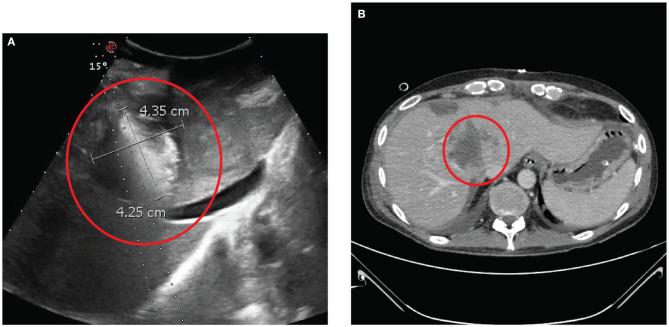

Cholangiocarcinoma (CCA) is the second most common primary tumor of the liver, and the recurrence after hepatic resection (HR), the only curative therapy, is linked with a worse prognosis. Systemic chemotherapy (SC) and liver loco-regional treatments, like trans-arterial chemoembolization (TACE) or radio embolization (TARE), have been employed for the treatment of unresectable intrahepatic metastasis (IM) with benefit on overall survival (OS), but SC has a limited effect on peritoneal metastasis (PM). In the last years, novel treatments like electrochemotherapy (ECT) with bleomycine (BLM) for IM and cytoreductive surgery with hyperthermic intraperitoneal chemotherapy (CRS and HIPEC) for PM have been applied in small series but with encouraging results. We hereby describe the first synchronous application of ECT and CRS and HIPEC for the treatment of a patient with IM and PM from CCA. A 47-year-old male patient with CCA underwent HR followed by adjuvant SC. After 14 months, for the occurrence of IM, the patient underwent a second HR and SC. Nonetheless, a new recurrence occurred and a third attempt of HR was proposed. Due to the intraoperative finding of unresectable IM with PM, no resective procedure was performed and the patient was referred to our center. CRS and HIPEC with cisplatin and mitomycin for PM and ECT with BLM on a bulky metastasis of the hepatic hilum were performed after 38 months from the first HR. The length of hospital stay was 19 days. At the computed tomography (CT) performed 11 days after treatment complete necrosis of the treated IM was detected. CT scan after 3 and 6 months and magnetic resonance after 9 months were performed. Necrosis of the treated IM nor PM but progression of the residual liver lesions was observed. After 3 months, the patient received SC and underwent TACE after 8 months and TARE after 9 months for the residual liver metastases. At 14 months from CRS and HIPEC, the patient is alive, in good condition, and with stability of the disease. The association of ECT and CRS and HIPEC could be safe and effective for the treatment of unresectable recurrent intrahepatic CCA with PM.

胆管癌(CCA)是肝脏第二常见的原发性肿瘤,肝切除(HR)作为唯一的根治性治疗方法,术后复发与预后较差相关。全身化疗(SC)以及肝局部区域治疗,如经动脉化疗栓塞术(TACE)或放射性栓塞术(TARE),已被用于治疗不可切除的肝内转移(IM),对总生存期(OS)有益,但SC对腹膜转移(PM)的疗效有限。近年来,新型治疗方法如用于IM的博来霉素(BLM)电化学疗法(ECT)以及用于PM的减瘤手术联合热灌注化疗(CRS和HIPEC)已在小样本中应用,但结果令人鼓舞。我们在此描述首例ECT与CRS及HIPEC同步应用于治疗一名患有CCA的IM和PM患者的情况。一名47岁的CCA男性患者接受了HR,随后进行辅助SC。14个月后,因出现IM,患者接受了第二次HR和SC。然而,又出现了新的复发,并提出进行第三次HR尝试。由于术中发现IM伴PM不可切除,未进行切除手术,患者被转诊至我们中心。在首次HR后的38个月,对PM进行了顺铂和丝裂霉素的CRS及HIPEC治疗,并对肝门部的一个巨大转移灶进行了BLM的ECT治疗。住院时间为19天。治疗后11天进行的计算机断层扫描(CT)显示,治疗的IM完全坏死。在3个月和6个月后进行了CT扫描,9个月后进行了磁共振检查。观察到治疗的IM和PM均无坏死,但残余肝脏病变进展。3个月后,患者接受了SC,8个月后进行了TACE,9个月后进行了TARE以治疗残余肝转移灶。在CRS和HIPEC后的14个月,患者存活,状况良好,疾病稳定。ECT与CRS及HIPEC联合应用对于治疗不可切除的复发性肝内CCA伴PM可能是安全有效的。